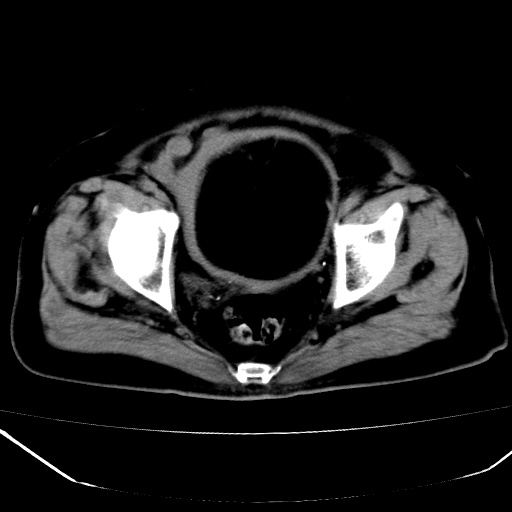

标题: CT18557:盆腔内包块,请指教

患者,女,74岁,无不适,b超示盆腔包块。

子宫前上方巨大脂性肿物,肿物边缘为较厚软组织密度影,其内缘欠光整,脂性密度中央见结节状软组织密度影“漂浮”,肿物与子宫前壁关系密切,考虑1脂肪瘤2皮样囊肿3肌瘤脂样变

ct值-90hu